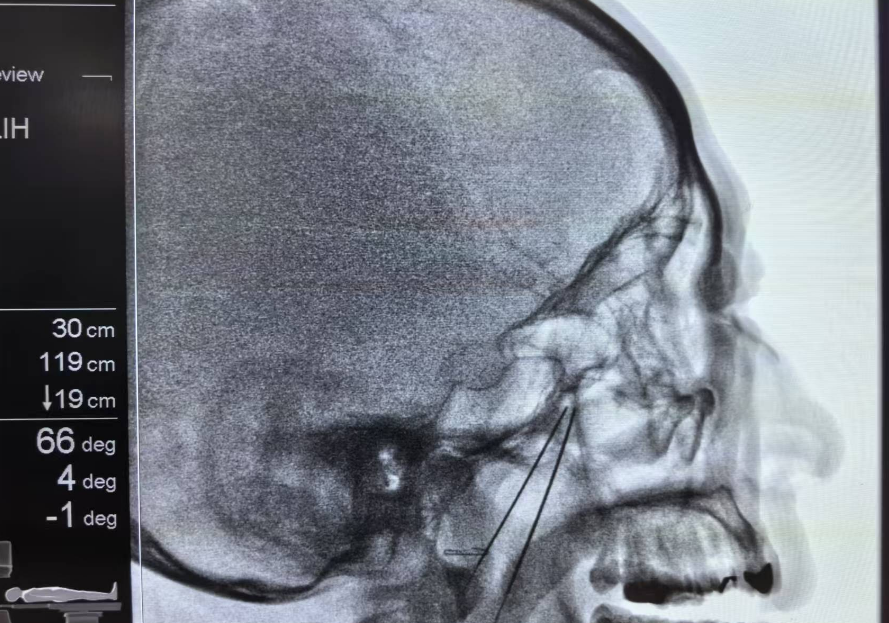

术中,贾一帆副教授在影像学精准引导下,仅用一根细穿刺针便成功定位目标神经节——蝶腭神经节,并通过温和的脉冲电流对其进行调控。整个微创手术过程仅耗时约15分钟。术后,张先生当即感觉症状缓解,术后面部无创口,观察一小时后即安全离院。近一年随访证实,其鼻炎症状基本未再复发。

科学研究证实,蝶腭神经节是调节鼻腔血管和腺体的“总开关”。贾一帆副教授介绍,脉冲射频调控术是在影像精准导航下,利用42℃以下的温和电流作用于该神经节,可有效提高交感神经兴奋性,调节神经肽释放,从而纠正紊乱的鼻黏膜生理功能,显著改善鼻塞、流涕等核心症状。